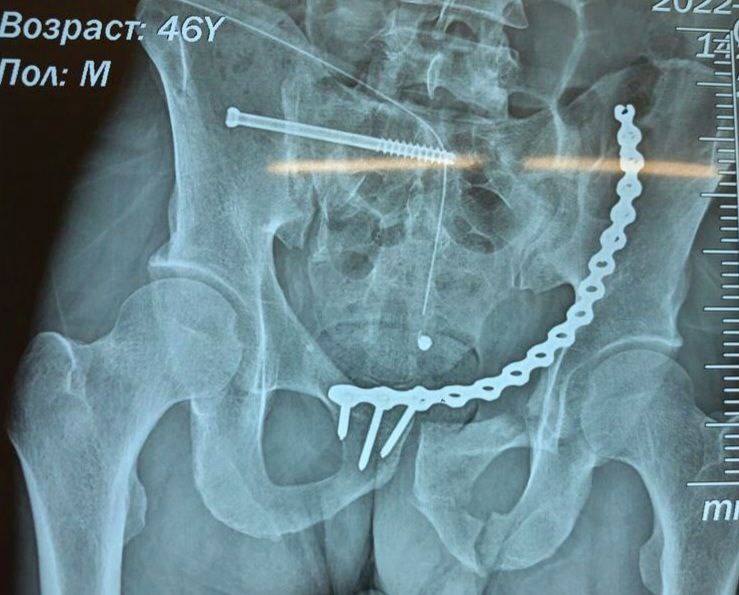

Мужчину 46 лет доставили в аппарате наружной фиксации, так как такой перелом являлся угрозой для жизни пациента в связи с опасением образования обширных гематом и жировой эмболии. В травматологическом отделении Александру была проведена компьютерная томография, в результате которой диагностировали: разрыв крестцово-подвздошного сочленения и перелом лонных костей таза.

Была проведена сложная операция по восстановлению тазового кольца и остеосинтез костей таза. После успешно проведенного хирургического вмешательства пациент в скором времени сможет передвигаться без ограничений.